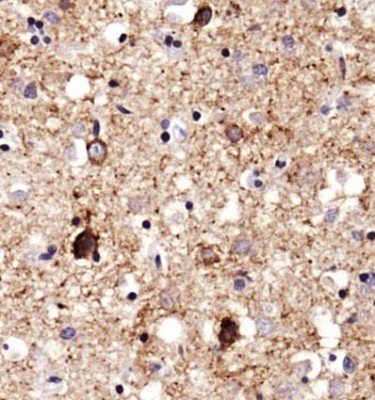

Supportive validation

- Submitted by

- antibodies-online (provider)

- Main image

- Experimental details

- IHC